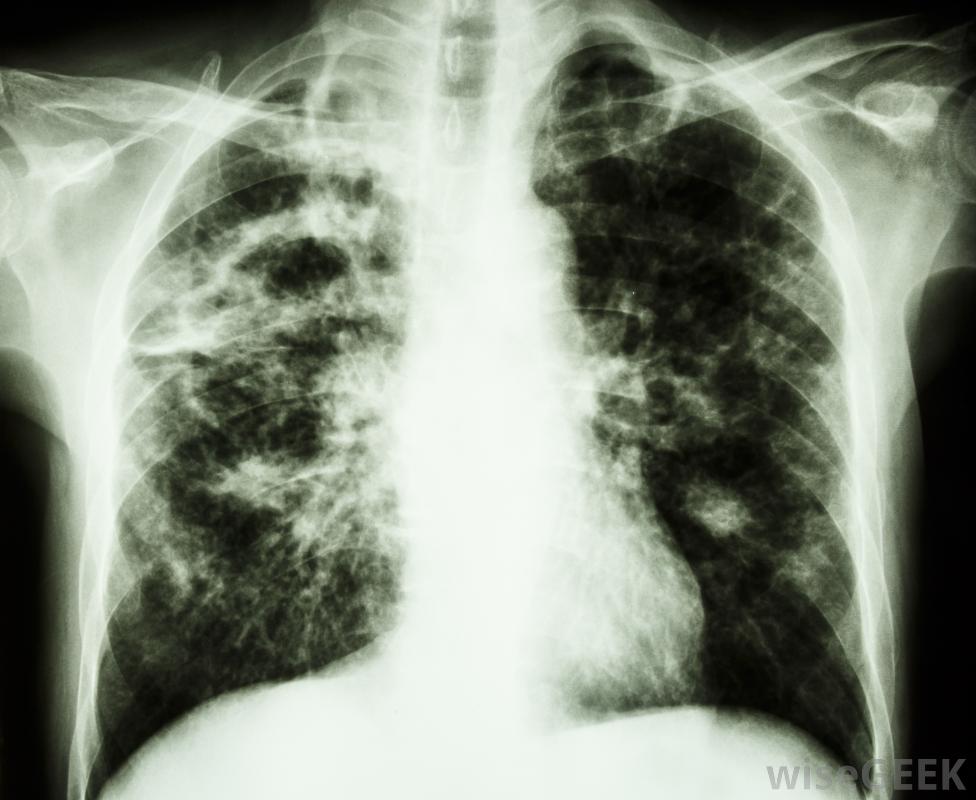

播散性疾病是一種疾病,它從最初的起源點或在體內的接觸點傳播到其他不是其特定攻擊目標的區域。通常,它通過血液供應或淋巴系統傳播,淋巴系統攜帶血漿中的白血球來抵抗感染。人類通常有兩種常見類型:一種是由癌癥引起的,腫瘤細胞擴散到全身;另一種是由細菌、真菌引起的傳染病,容易成為一種傳播性疾病的感染包括艾滋病、肺結核和皮下皮膚感染,如引起壞疽的皮膚感染盜汗和發燒。癌癥被認為是一種播散性疾病,因為它利用身體的血液進行轉移,從20世紀50年代起,化療藥物就開始治療癌癥的播散性疾病,這種藥物可以在腫瘤細胞擴散的過程中殺死腫瘤細胞。20世紀70年代,一些抗生素也被發現對癌癥有有益的作用,如放線菌素D和博萊霉素,因此,這些藥物與化療的聯合治療開始了。在1965年的聯合治療中,當加入復方順鉑時,新方案中高達70%的患者表現出陽性反應。到2011年,這仍然是治療癌癥的常用方法,根據癌癥類型的不同,61%到83%的患者通過新的藥物組合達到無癌狀態結核病被認為是高度傳染性的,空氣傳播疾病。肺結核是由空氣中的水滴攜帶的結核分枝桿菌感染肺部引起的疾病。在極少數情況下,結核病會成為一種播散性疾病它會擴散到身體的許多部位,如骨骼、腸道和心臟內壁。最容易感染播散型肺結核的人是那些免疫系統較弱的人,如老年人、艾滋病患者和嬰兒。與癌癥一樣,播散型肺結核的治療方法為10種或更多種不同的化學制劑和抗生素。結核病最常見的是在肺部生存和繁衍,盡管它可能傳播到其他地區截至2011年,醫學科學已經發現了一系列可能導致傳播性疾病的感染性有機體,例如,幾種棘阿米巴(acanthamoba)的細菌,即使不需要人類宿主來生存,也可以像病毒一樣生活,也沒有特定的人或動物攜帶者膿腫是導致肺部、軟組織和艾滋病相關的播散性疾病的原因,透明絲孢菌組的真菌也會引起播散性疾病,這在免疫抑制的個體和最近接受過移植的人中最常見。該組中引起感染性疾病的最常見真菌種類包括鐮刀菌屬spp.,Acremoniumspp,骨癌是一種播散性疾病src="/img/0803/man-using-tissue-near-female-doctor-wearing-mask.jpg"/>肺結核的癥狀可能包括疲勞和咳嗽。不遵循有效治療方案的結核病患者會產生抗生素耐藥性。